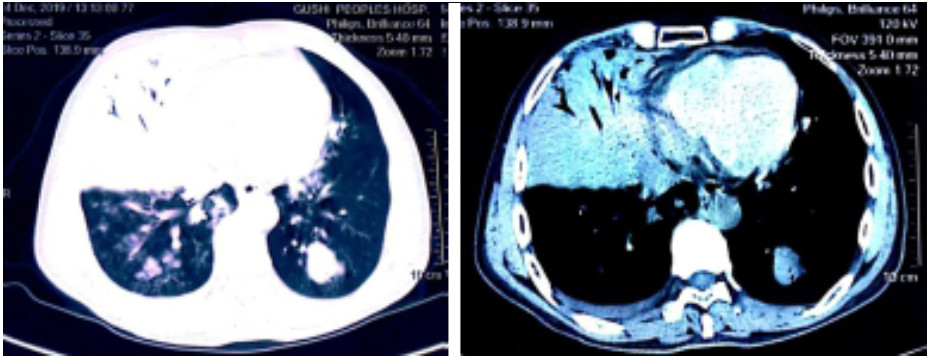

1 资料与方法患者,男,54岁。因“咳嗽咳痰伴发热12 d”于2019年12月14日收入院。12 d前受凉后出现咳嗽,咳少量痰,发热,在天津某诊所拟“感冒”治疗后,症状无好转。7 d前至宁波某医院门诊治疗,症状未见改善。2 d前咳嗽咳痰加重,大量灰褐色痰,有腥臭味,并出现呼吸急促及高热(最高39.0 ℃)。1 d前在河南某医院胸部CT示右肺上叶及中叶大片实变影,左肺上下叶可见散在团块状密度增高影(图 1),住院1 d后出院,于12月14日晚收入我院。上述治疗用药患方均未能提供。患者10年前因胃溃疡行胃部分切除术,无吸烟酗酒病史,无牙周病病史。患者为建筑工人,平日常辗转各建筑工地工作。体格检查:体温39.3 ℃,心率155次/min,呼吸35次/min,血压131/81 mmHg(1 mmHg=0.133 kPa),吸氧3 L/min时经皮氧饱和度90%,双肺呼吸音粗,可闻及粗湿性啰音。入科后实验室检查:白细胞5.03×109/L,中性粒细胞百分比0.97,淋巴细胞百分比0.04,血红蛋白124 g/L,血小板137×109/L;C反应蛋白122.5 mg/L,降钙素原42.42 ng/mL,白介素-6 > 5 000 pg/mL;生化:白蛋白16.7 g/L,谷草转氨酶159 U/L,血肌酐208 μmol/L,尿素氮25.07 mmol/L,乳酸2.52 mmol/L。血浆D-二聚体3 630 μg/L,肌红蛋白 > 4 057 ng/mL,肌酸激酶1 471 U/L。空腹血糖8.4 mmol/L,糖化血红蛋白6.2%,人类免疫缺陷病毒抗体、甲型及乙型流感病毒抗体、痰抗酸染色均阴性。G试验 < 10 pg/mL,GM试验0.3 pg/mL,癌胚抗原1.66 ng/mL,甲胎蛋白0.7 ng/mL,T细胞亚群:总T淋巴细胞计数106/μL,CD4+T 54/μL,CD8+T 40/μL。

| 图 1 患者2019年12月14日胸部CT结果(右肺上叶及中叶大片实变影,左肺上下叶可见散在团块状密度增高影) |